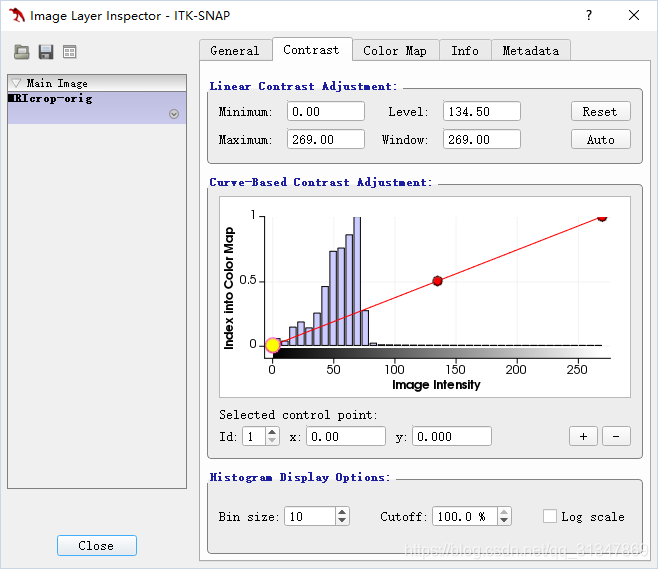

调整图像对比度:Tools -> Image Contrast -> Contrast Adjustment

绘图区域显示了图像强度和现实强度的映射,如红线所示

红线上黄色的点为 “控制点”,可以改变映射的形状

蓝色的直方图是灰度图图的各灰度级

从直方图可以看出,当前有很多强度值过低(在后三分之一),所以要提高对比度,需要先调整映射方式。

调整方法:

1)更改 Window 数值,Enter 键生效。Level 值是最左边 control point 的强度值,Window 值是最左和最右 control

point 的差

2)直接用鼠标调整 “控制点”,最左边的点决定了最小强度从哪里开始,最右边的点决定了最大强度从哪里开始

可以根据需要添加 control point,以调整出需要的 mapping curve